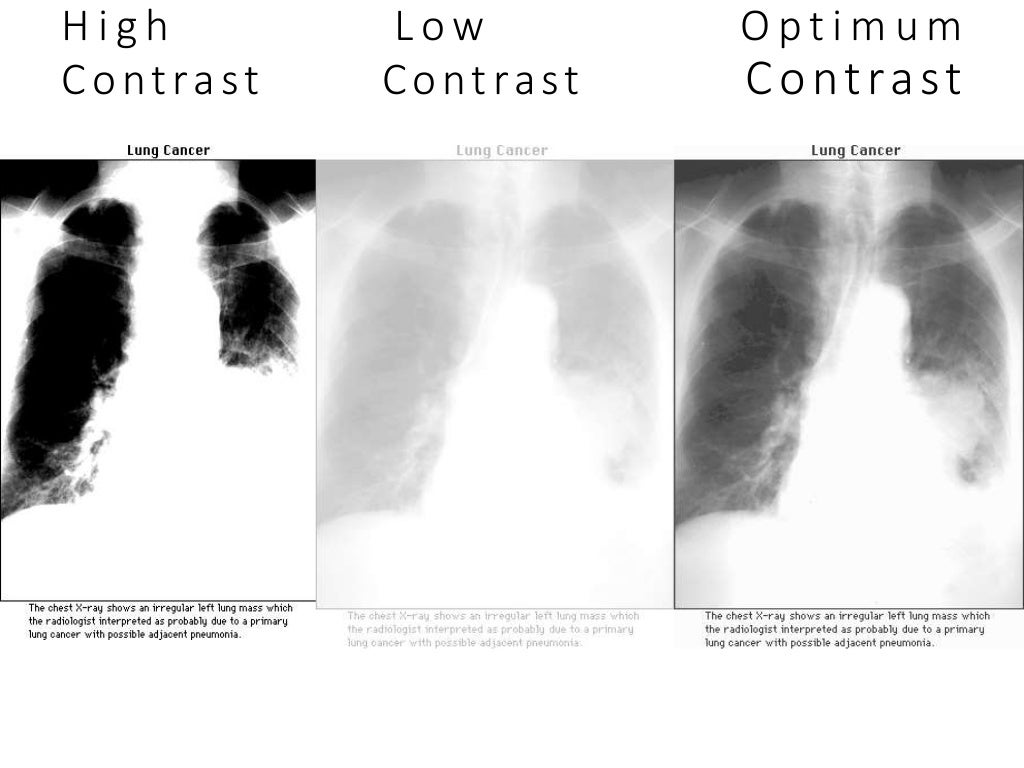

Diagnostics Free FullText Suboptimal Chest Radiography and What Does Ap Mean In Radiology Ap portable view of the chest; Magnification is exaggerated further by. The erect anteroposterior chest view is an alternative to the pa view when the patient is too unwell to tolerate standing or leaving the bed 1. What’s the difference between ap, pa, lat and oblique views? This section lists what the radiologist saw in each area of the. Pa. What Does Ap Mean In Radiology.